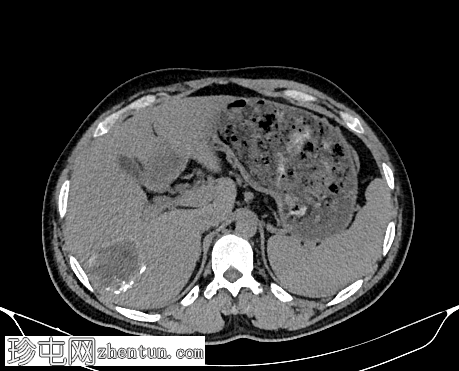

轴位增强扫描(延迟期)

3.jpg

肝脏VII段可见一边界清晰的囊性病变,内部有分隔,囊壁可见钙化。

右肾中央部分(肾门)可见一囊性病变,中心可见基质,周围可见子囊。该病变与肾盂肾盏无交通。病变周围可见两处高密度影,位于上、中肾盏,无法区分是结石还是病变壁钙化。另可见上极肾盏中度扩张。